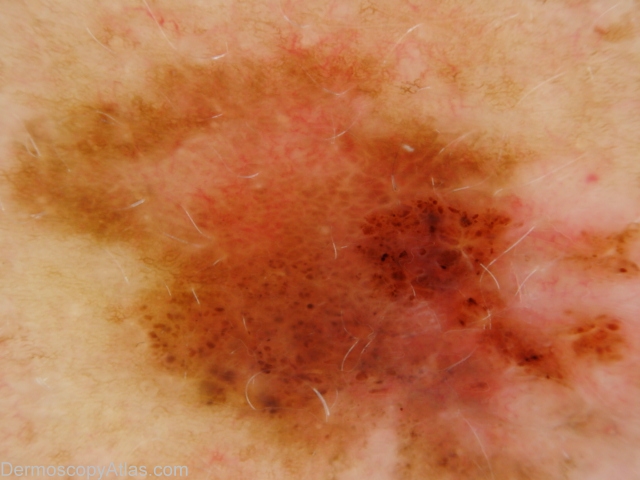

Site: Abdomen

Diagnosis: Melanoma invasive

Sex: F

Age: 54

Type: Dermlite Polarised

Submitted By: Ian McColl

Description: Pigmented lesion on the back showing pigment dots, asymmetry of pigmentation and a negative network.

History: This lesion had developed over several months. It was brought to her attention by being itchy. It was a superficial spreading melanoma, 0.35mm thick , Clark level 2. The histopathology did show some features of regression.